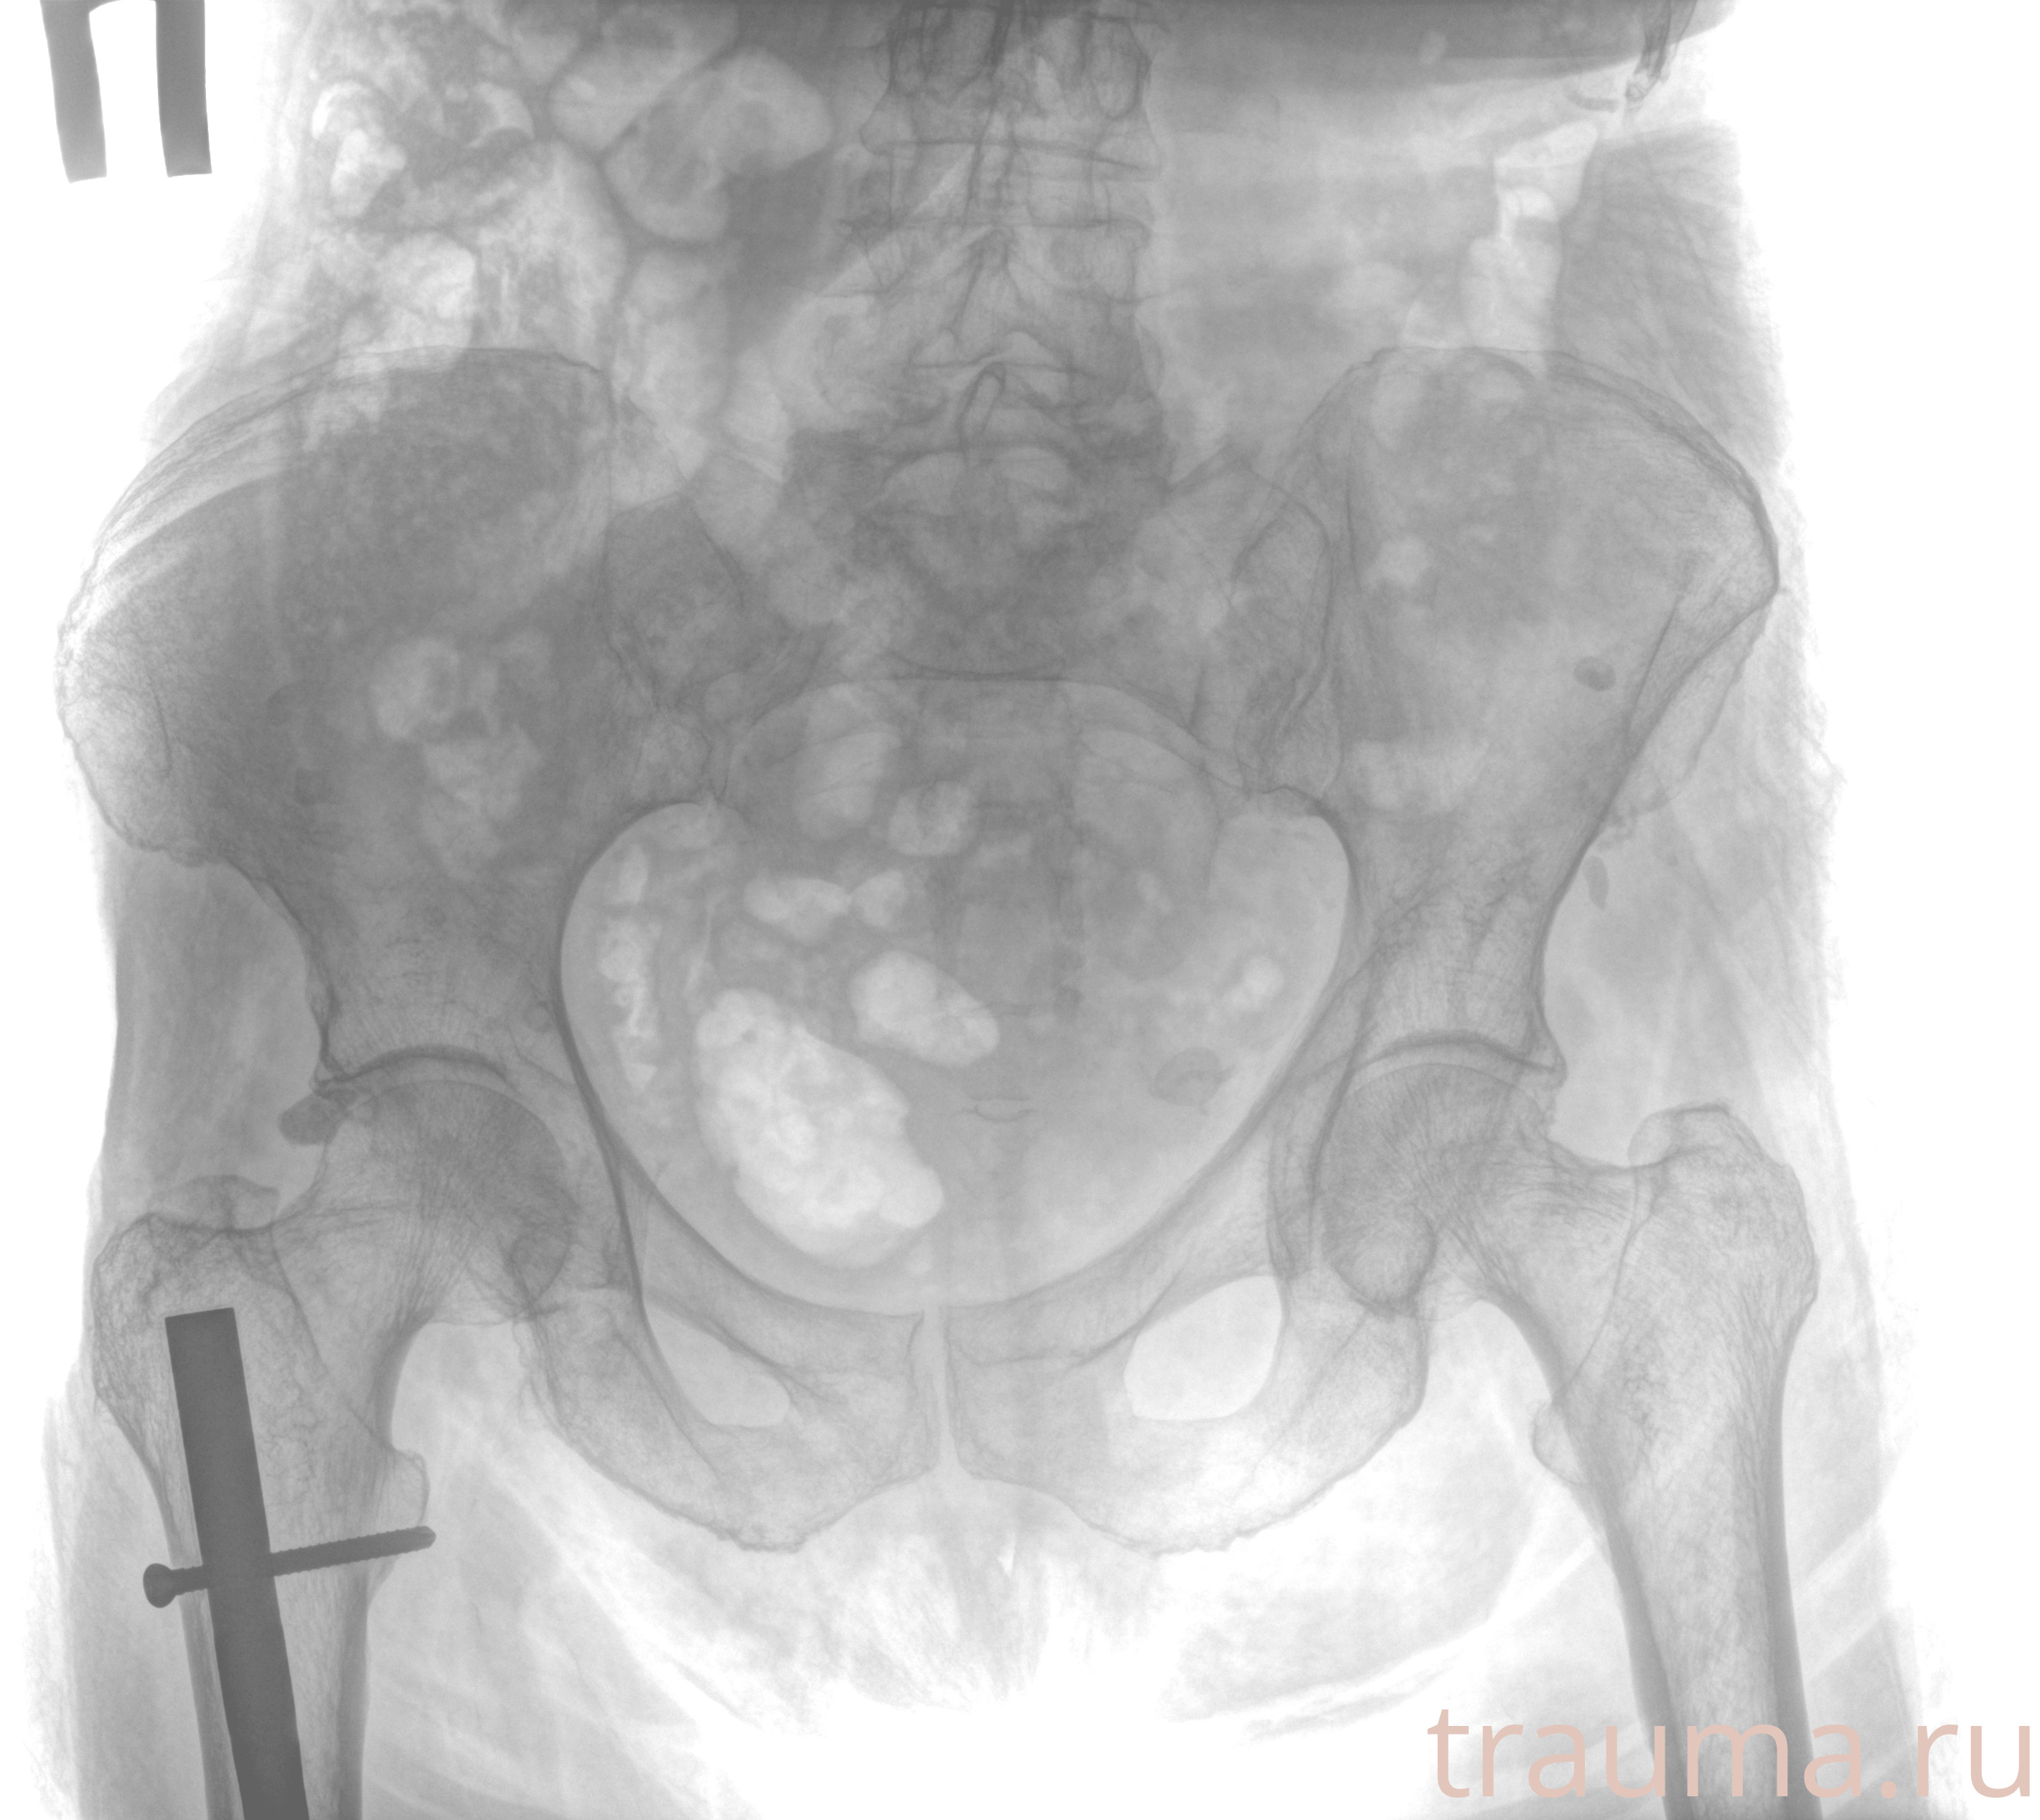

Рентген на дому: по вашему адресу приезжает врач-рентгенолог, травматолог-ортопед с мобильным рентгеновским аппаратом, проводит диагностику травмы или заболевания, делает необходимые рентгенограммы, дает рекомендации по дальнейшему лечению. Получить качественные снимки в домашних условиях возможно благодаря уникальной методике, разработанной МосРентген Центром для института  Склифосовского